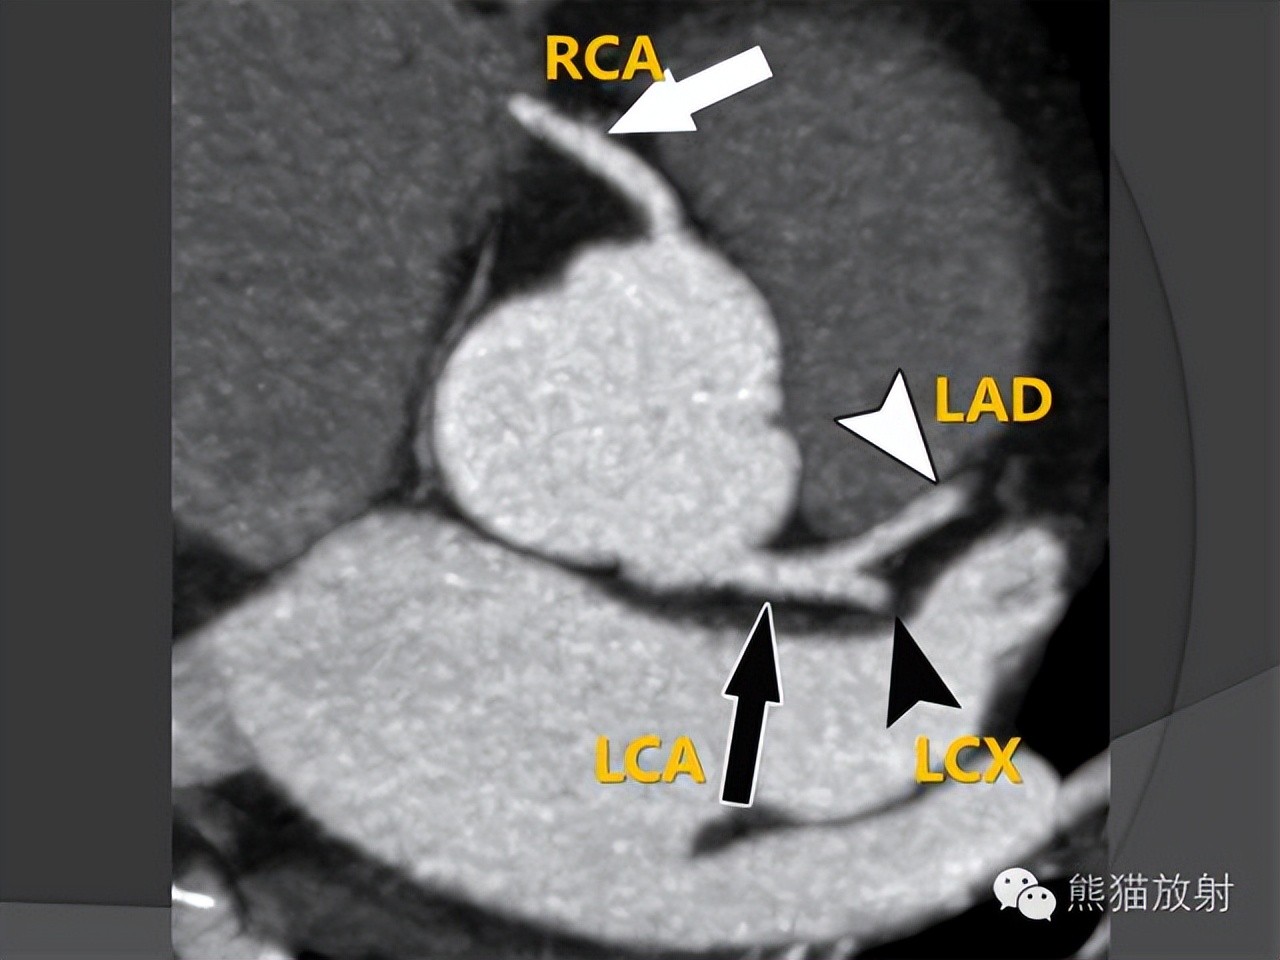

冠状动脉CTA解剖